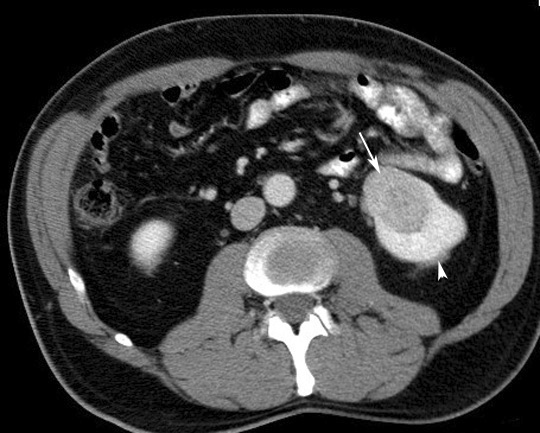

CT scan in a patient with Renal Cell Carcinoma

• Arrow points to solid hypodense mass in left kidney .

• Arrowheads poing to normal parenchymal enhancement.